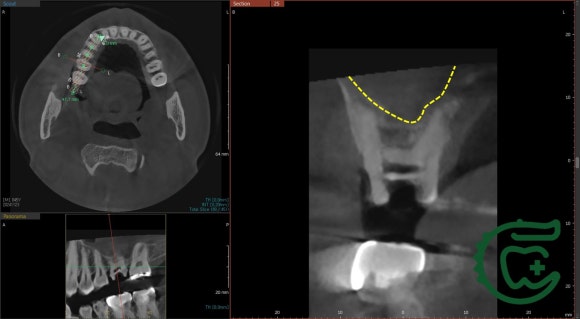

타치과에서 재신경치료를 받으시던 도중에

저희 치과로 오셨습니다.

상악동에는 염증이 꽉 찬 상태.

(=윗 어금니와 코 사이, 광대 밑에 있는 빈공간)

물론,

치아에서 기원한 염증이 아닐 수도 있습니다.

비염이 있거나 코감기에 든 상태라면

CT 상에서 이렇게 보일 수 있죠.